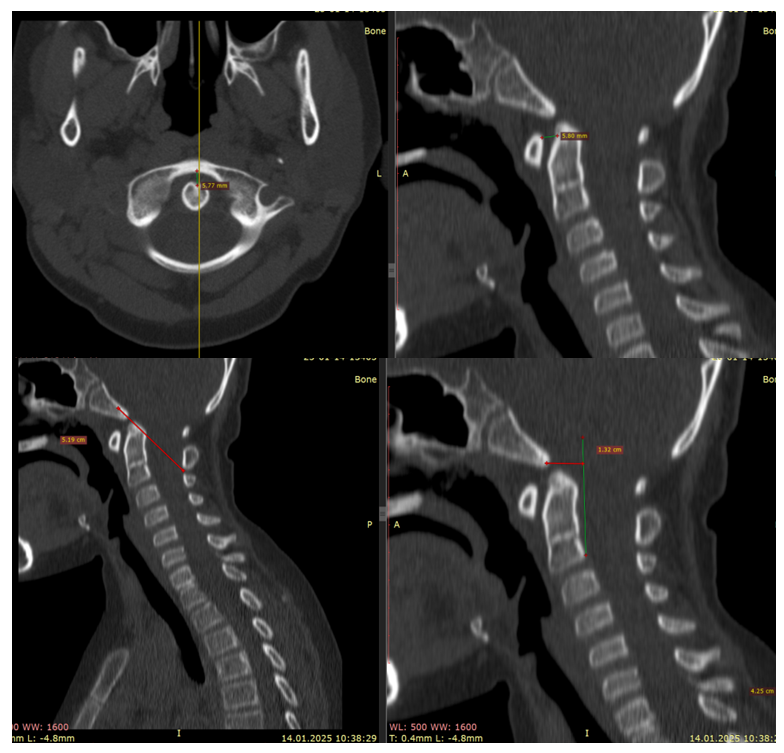

Craniometry and Neuroimaging The frequency of abnormalities in key metrics differed between groups. In basilar invagination, abnormal values of the Harris line, ADI, and Cruveilhier joint were more frequently observed; in Chiari malformations, combined abnormalities of the Grabb-Oakes curve, Chamberlain/McGregor lines, and dorsal balance indices (Schmidt-Fischer, CVA) were more common. | Figure 1. CT craniometric indices (Harris line, atlanto‑dens interval, Wackenheim line) indicating ventral compression and craniocervical instability |